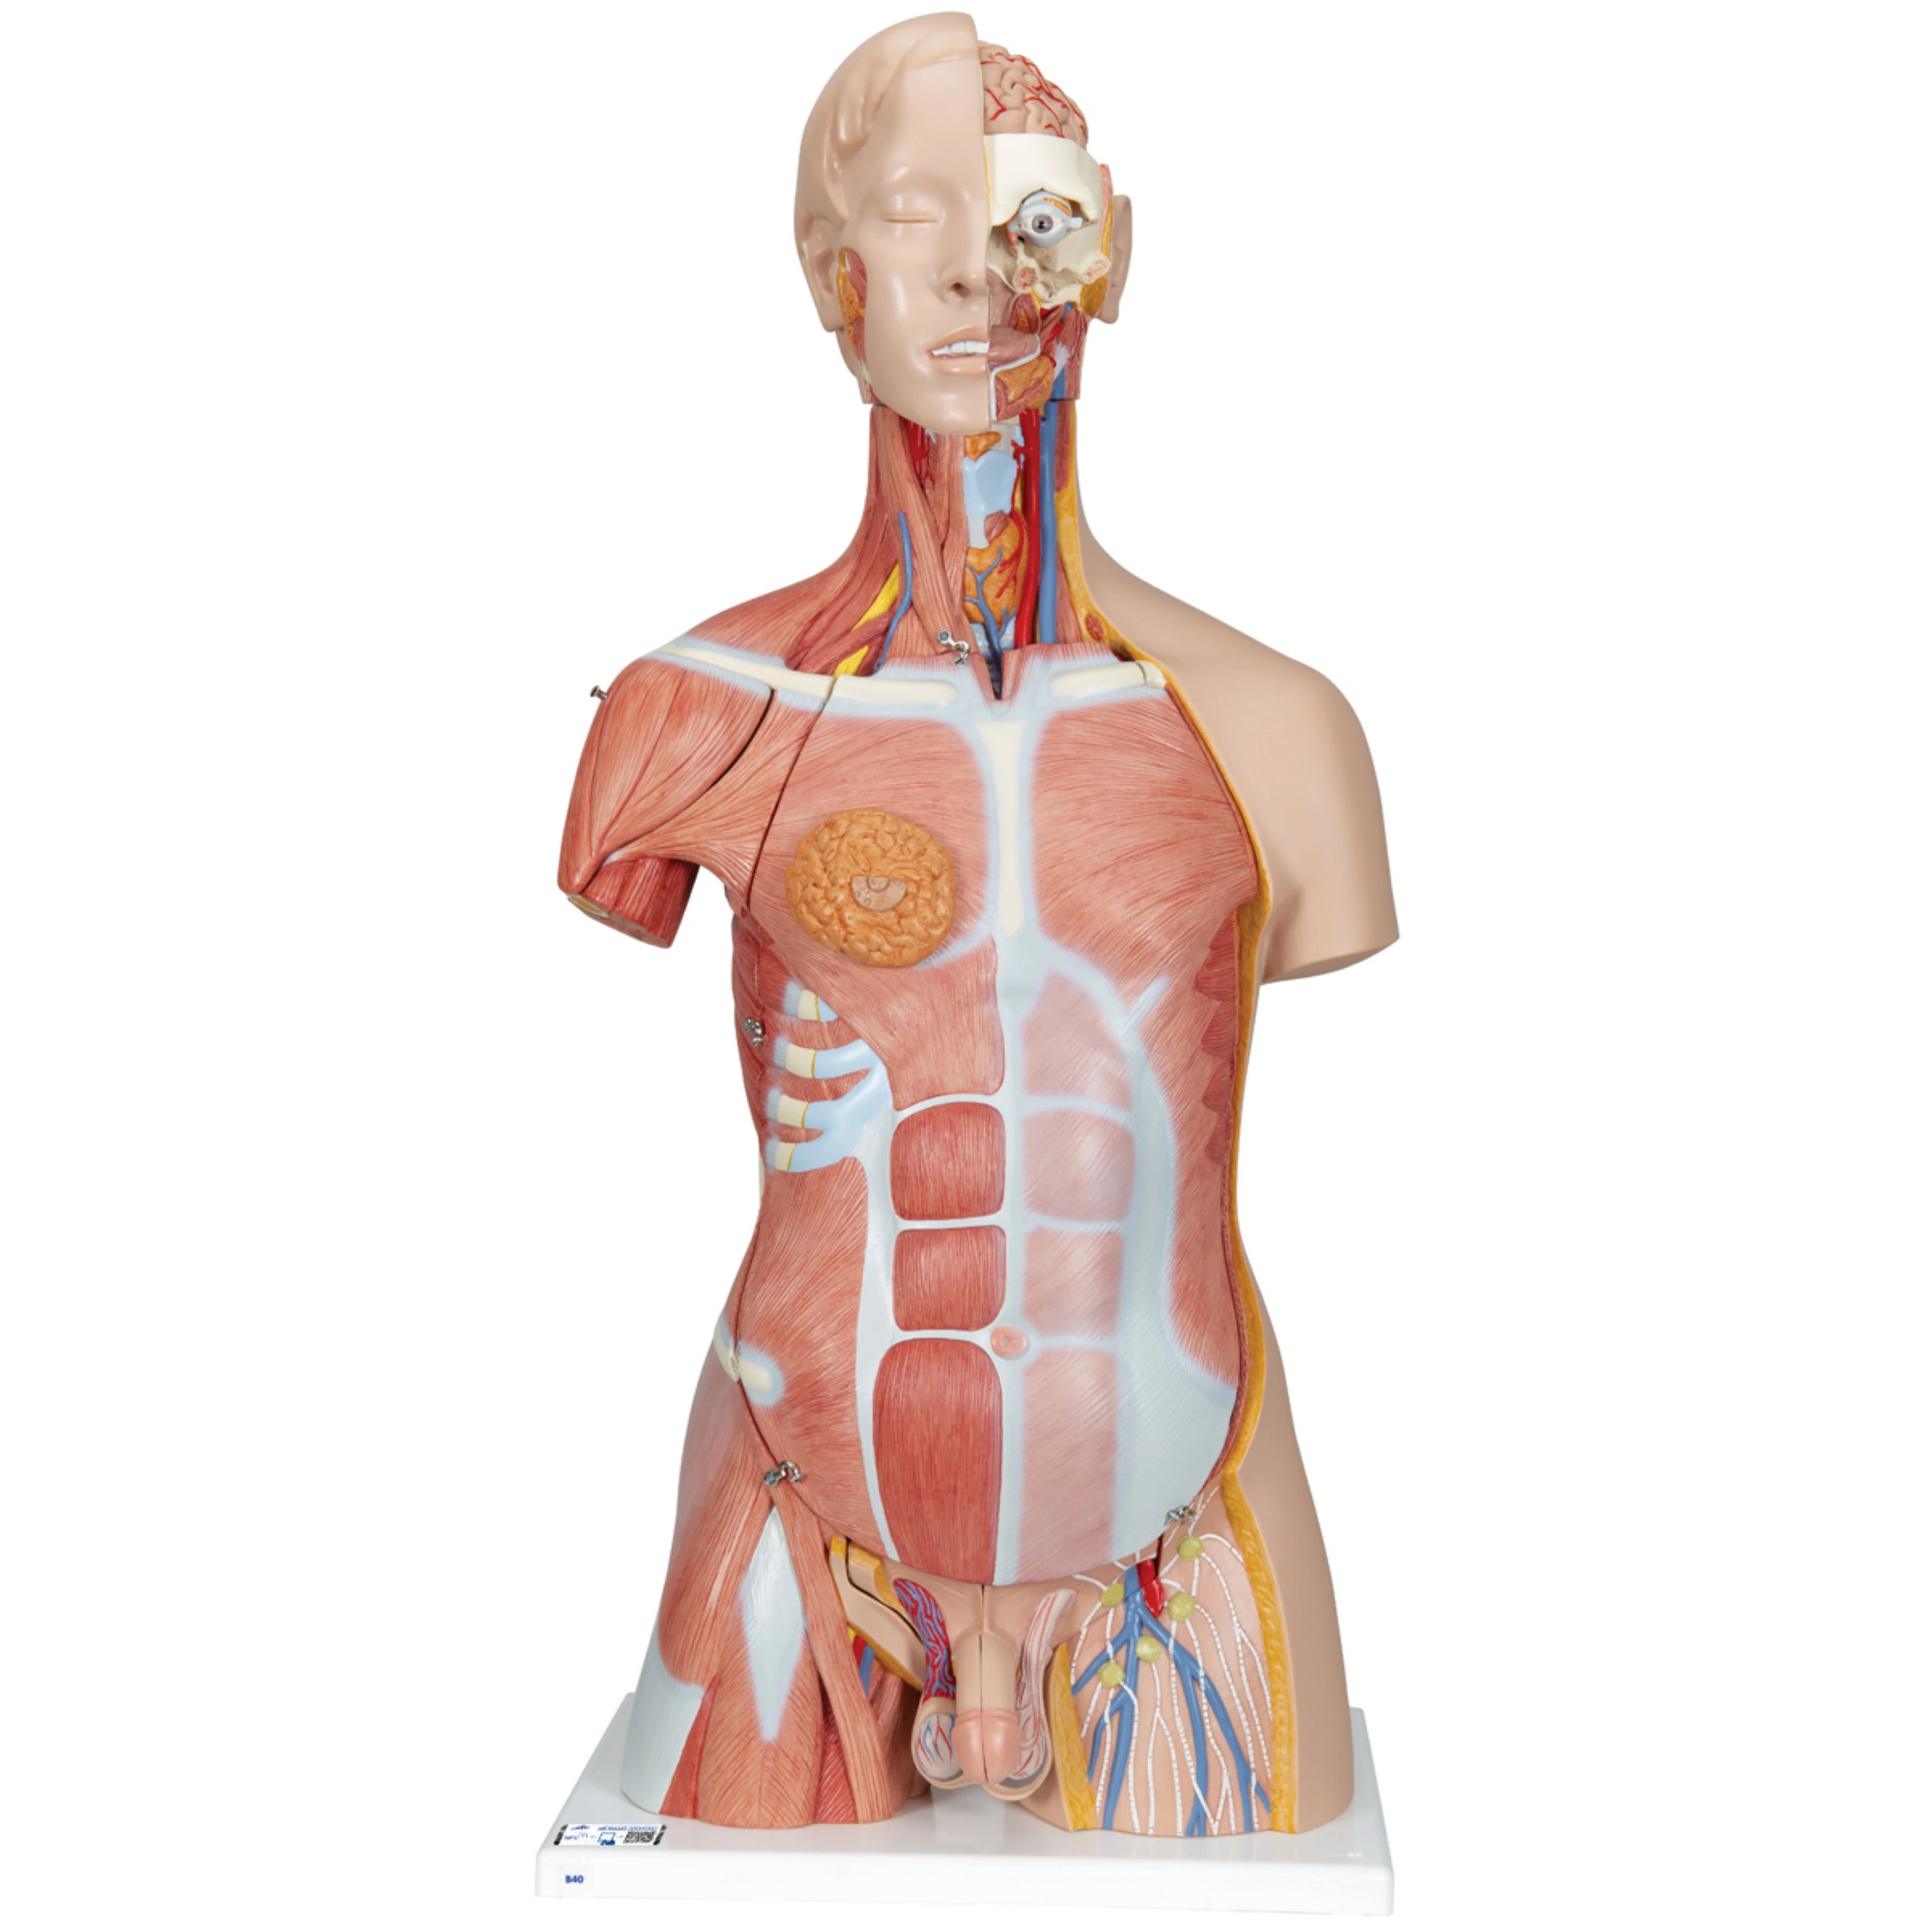

Torso clásico con espalda abierta, 18 partes - 3B Smart Anatomy

Precio de venta$33,762.96